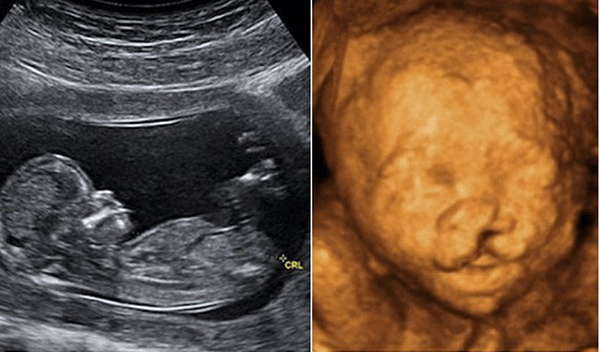

Có nhiều hình thức siêu âm thai phổ biến được áp dụng trong từng thời kì của quá trình mang thai là siêu âm 2D, 3D, 4D. Tùy theo mục đích của việc siêu âm thai mà bác sĩ sẽ chỉ định và thực hiện các hình thức siêu âm phù hợp.

Siêu âm 2D

Là hình thức siêu âm cho hình ảnh đen trắng được áp dụng nhiều nhất trong siêu âm thai. Dựa vào hình ảnh sóng âm thanh trên màn hình mà bác sĩ có thể phát hiện được có thai hay không, thai đã vào tử cung chưa.

Siêu âm thai 2D thường được chỉ định khi thai còn nhỏ, siêu âm 3D, 4D khó phát hiện. Sóng siêu âm 2D cũng rất nhỏ nên không ảnh hưởng đến thai nhi.

Siêu âm 3D

Là bước cải tiến từ siêu âm 2D ra đời vào năm 1980, hình ảnh thai nhi siêu âm 3D được chụp lần đầu tiên vào năm 1986. Siêu âm cho hình ảnh 3 chiều giúp cha mẹ có thể nhìn thấy hình ảnh của bé sống động hơn, thấy được cấu trúc mặt của bé qua hình ảnh màu.

Siêu âm 4D

Cho hình ảnh siêu âm 4 chiều có thể thấy được là sự chuyển động của bé qua đoạn băng ghi hình. Hình thức siêu âm này không chỉ giúp bác sĩ thấy rõ được những bất thường ở cấu trúc mặt, cơ quan sinh dục… mà còn là cách cha mẹ lưu giữ kỉ niệm cho bé.